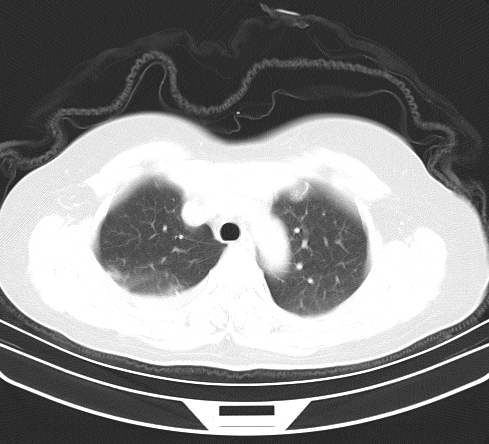

以下是引用余辉在2009-2-19 20:10:00的发言:[br]多考虑急性感染性病变,右中叶尚可见多枚小斑片状影,多为化脓性肺炎,双侧胸腔积液

以下是引用随光逐影在2009-2-19 20:33:00的发言:[br]1)考虑右肺炎症;建议抗炎治疗后复查。2)双侧胸腔积液(以右侧为甚)。

以下是引用花凤凰在2009-2-19 20:46:00的发言:[br]病人有发热,胸痛急性起病,主要病变位于右肺中叶外侧段,呈楔行改变,位于外带胸膜下,考虑为肺梗塞可能!!!!!!!!!!!!!!!!!!!!!!!!!!!!!!!!!!!